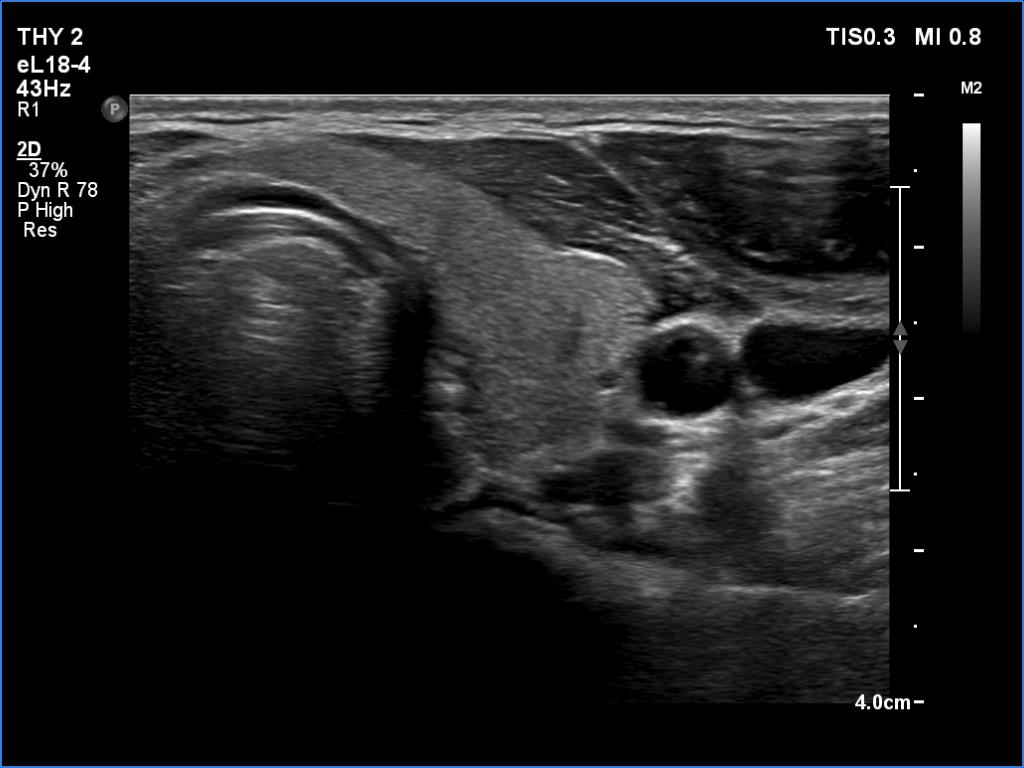

Ultrasound. Both lobes were echonormal and intact. The vascularity was average.

Diagnosis. A healthy thyroid with great probability.